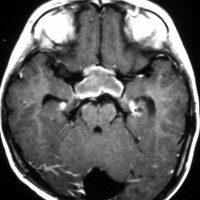

化学療法が有効なのは,上の画像のようにガドリニウム増強で強く増強されるタイプです,またT2強調画像で強い高信号になるものほど化学療法が有効です,要するに毛様粘液性星細胞腫の要素に化学療法が有効であるということです

この毛様細胞性星細胞腫はガドリニウムでほとんど増強されません(右側のMRI)から,化学療法を行っても小さくなりませんので,手術摘出する必要があります,実際に視床下部から発生したもの視交叉が犯されておらず,手術亜全摘出できました